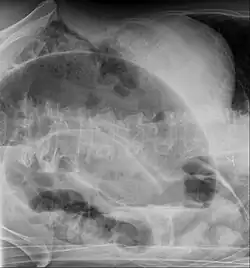

Die Diagnose wird anhand der Klinik und Röntgenaufnahmen des Abdomens (ggf. mit Kontrastmittel), neuerdings auch mittels Ultraschall, gestellt. Die Diagnosefindung insbesondere im Neugeborenenalter kann schwierig sein, da die Klinik lediglich eine Schwellung des Bauches zeigt, und das Röntgenbild unspezifisch sein kann.

Beim Volvulus des Colon sigmoideum findet sich bedingt durch eine massive Überblähung dieses Darmanteils häufig ein so genanntes Kaffeebohnenzeichen (engl. Coffee-bean sign), bei dem eine aufsteigende Schlinge dicht an eine absteigende gelegt ist, so dass sich die Kontur einer übergroßen Kaffeebohne ergibt. Bei bereits stattgehabter Perforation findet sich im Röntgenbild so genannte „freie Luft“.

Bei Erwachsenen wird häufig beim Bild eines akuten Abdomens auch die Computertomographie eingesetzt. Als typisches Zeichen neben der massiven Überblähung beim Volvulus kann hiermit auch die Drehung der Mesenterialwurzel mit ihren Gefäßen (Whirlpool-Zeichen) gezeigt werden.